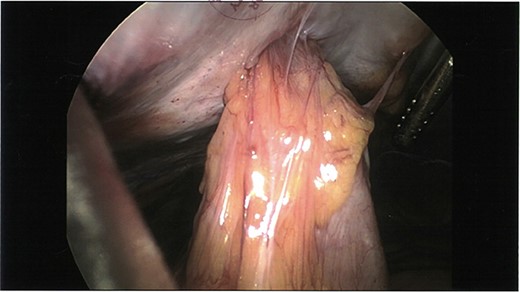

Initial laparoscopic view of the loop of small bowel tethered to the anterior abdominal wall.

The patient was taken to theatre for a diagnostic laparoscopy where a loop of small bowel was found tethered to the anterior abdominal wall (Fig. 2). A decision was made for a local transverse incision over collection and the sinus tract was excised to find a small-bowel perforation around the RapidPort with an abscess cavity extending through the subcutaneous tissue to the skin. The bowel was run and no other areas of compromise were noted. Additionally, there was no evidence of soft tissue injury and the omentum appeared intact. The patient underwent a successful small-bowel resection and made an uneventful recovery. Histopathology confirmed a full-thickness defect in the resected small bowel segment with adjacent acute serositis.